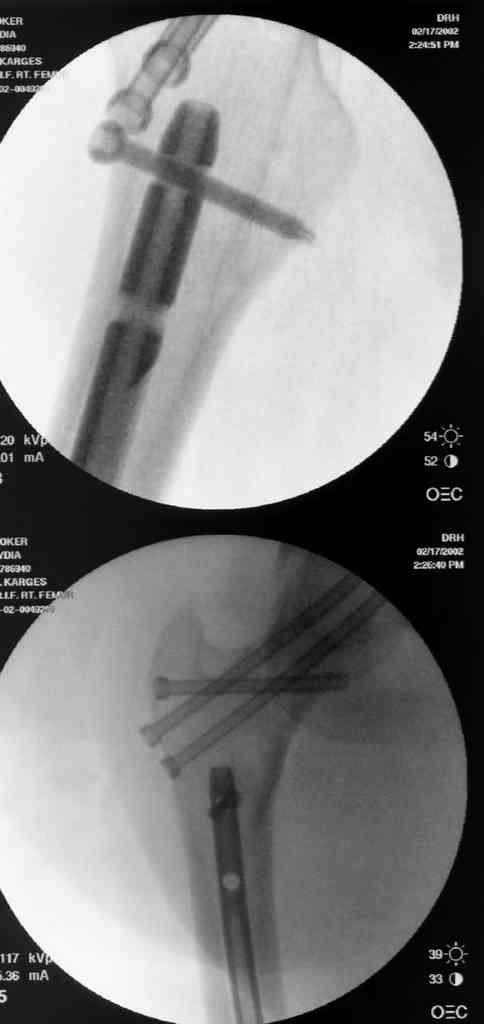

На снимках ложный сустав шейки бедра, несостоятельность фиксации. По положению шурупа можно предсказать ложный сустав, например, если screw backup за кортикальный слой около 15-20 мм, и также изменение угла от первоначального.

№2-3 типичная ошибка несоблюдения концепции параллельности шурупов, нарушение-фиксация поперечным допольнительным шурупом для приближения отломка в результате не сработало метод параллельных шурупов

№4 результат на КТ